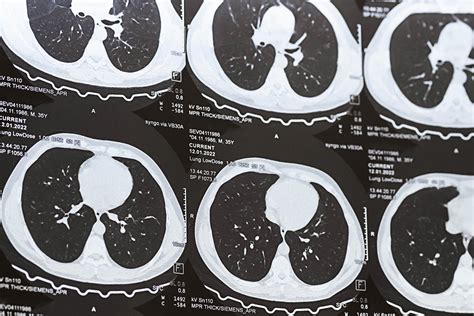

Lung nodules are small, round or oval-shaped growths that appear in the lung tissue. They can be detected through various imaging techniques, such as chest X-rays, CT scans, and MRI scans. These nodules can be caused by a variety of factors, including infections, inflammation, and cancer. The size of the nodule is a critical factor in determining its nature and the appropriate course of action.

Imaging Techniques for Measuring Lung Nodules

• CT Scan: Computed tomography (CT) scans offer high-resolution images and are more sensitive in detecting smaller nodules. They are often used for follow-up and monitoring.